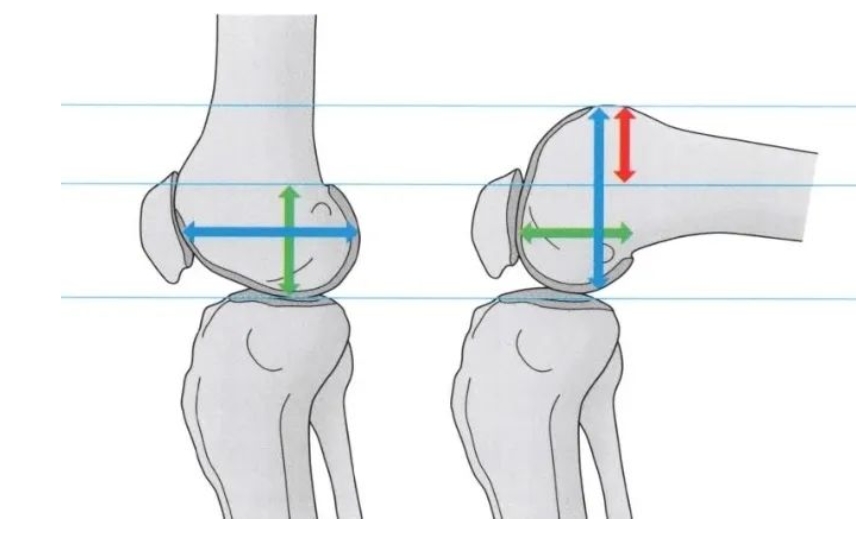

米琨:如何规范进行Oxford牛津单髁置换手术!